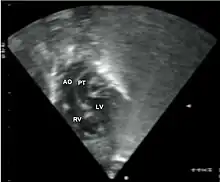

Echocardiography of a complex transposition with a ventricular septal defect and pulmonary stenosis.

Abbreviations: LV and RV=left and right ventricle, PT=pulmonary trunk, VSD=ventricular septal defect, PS=pulmonary stenosis.